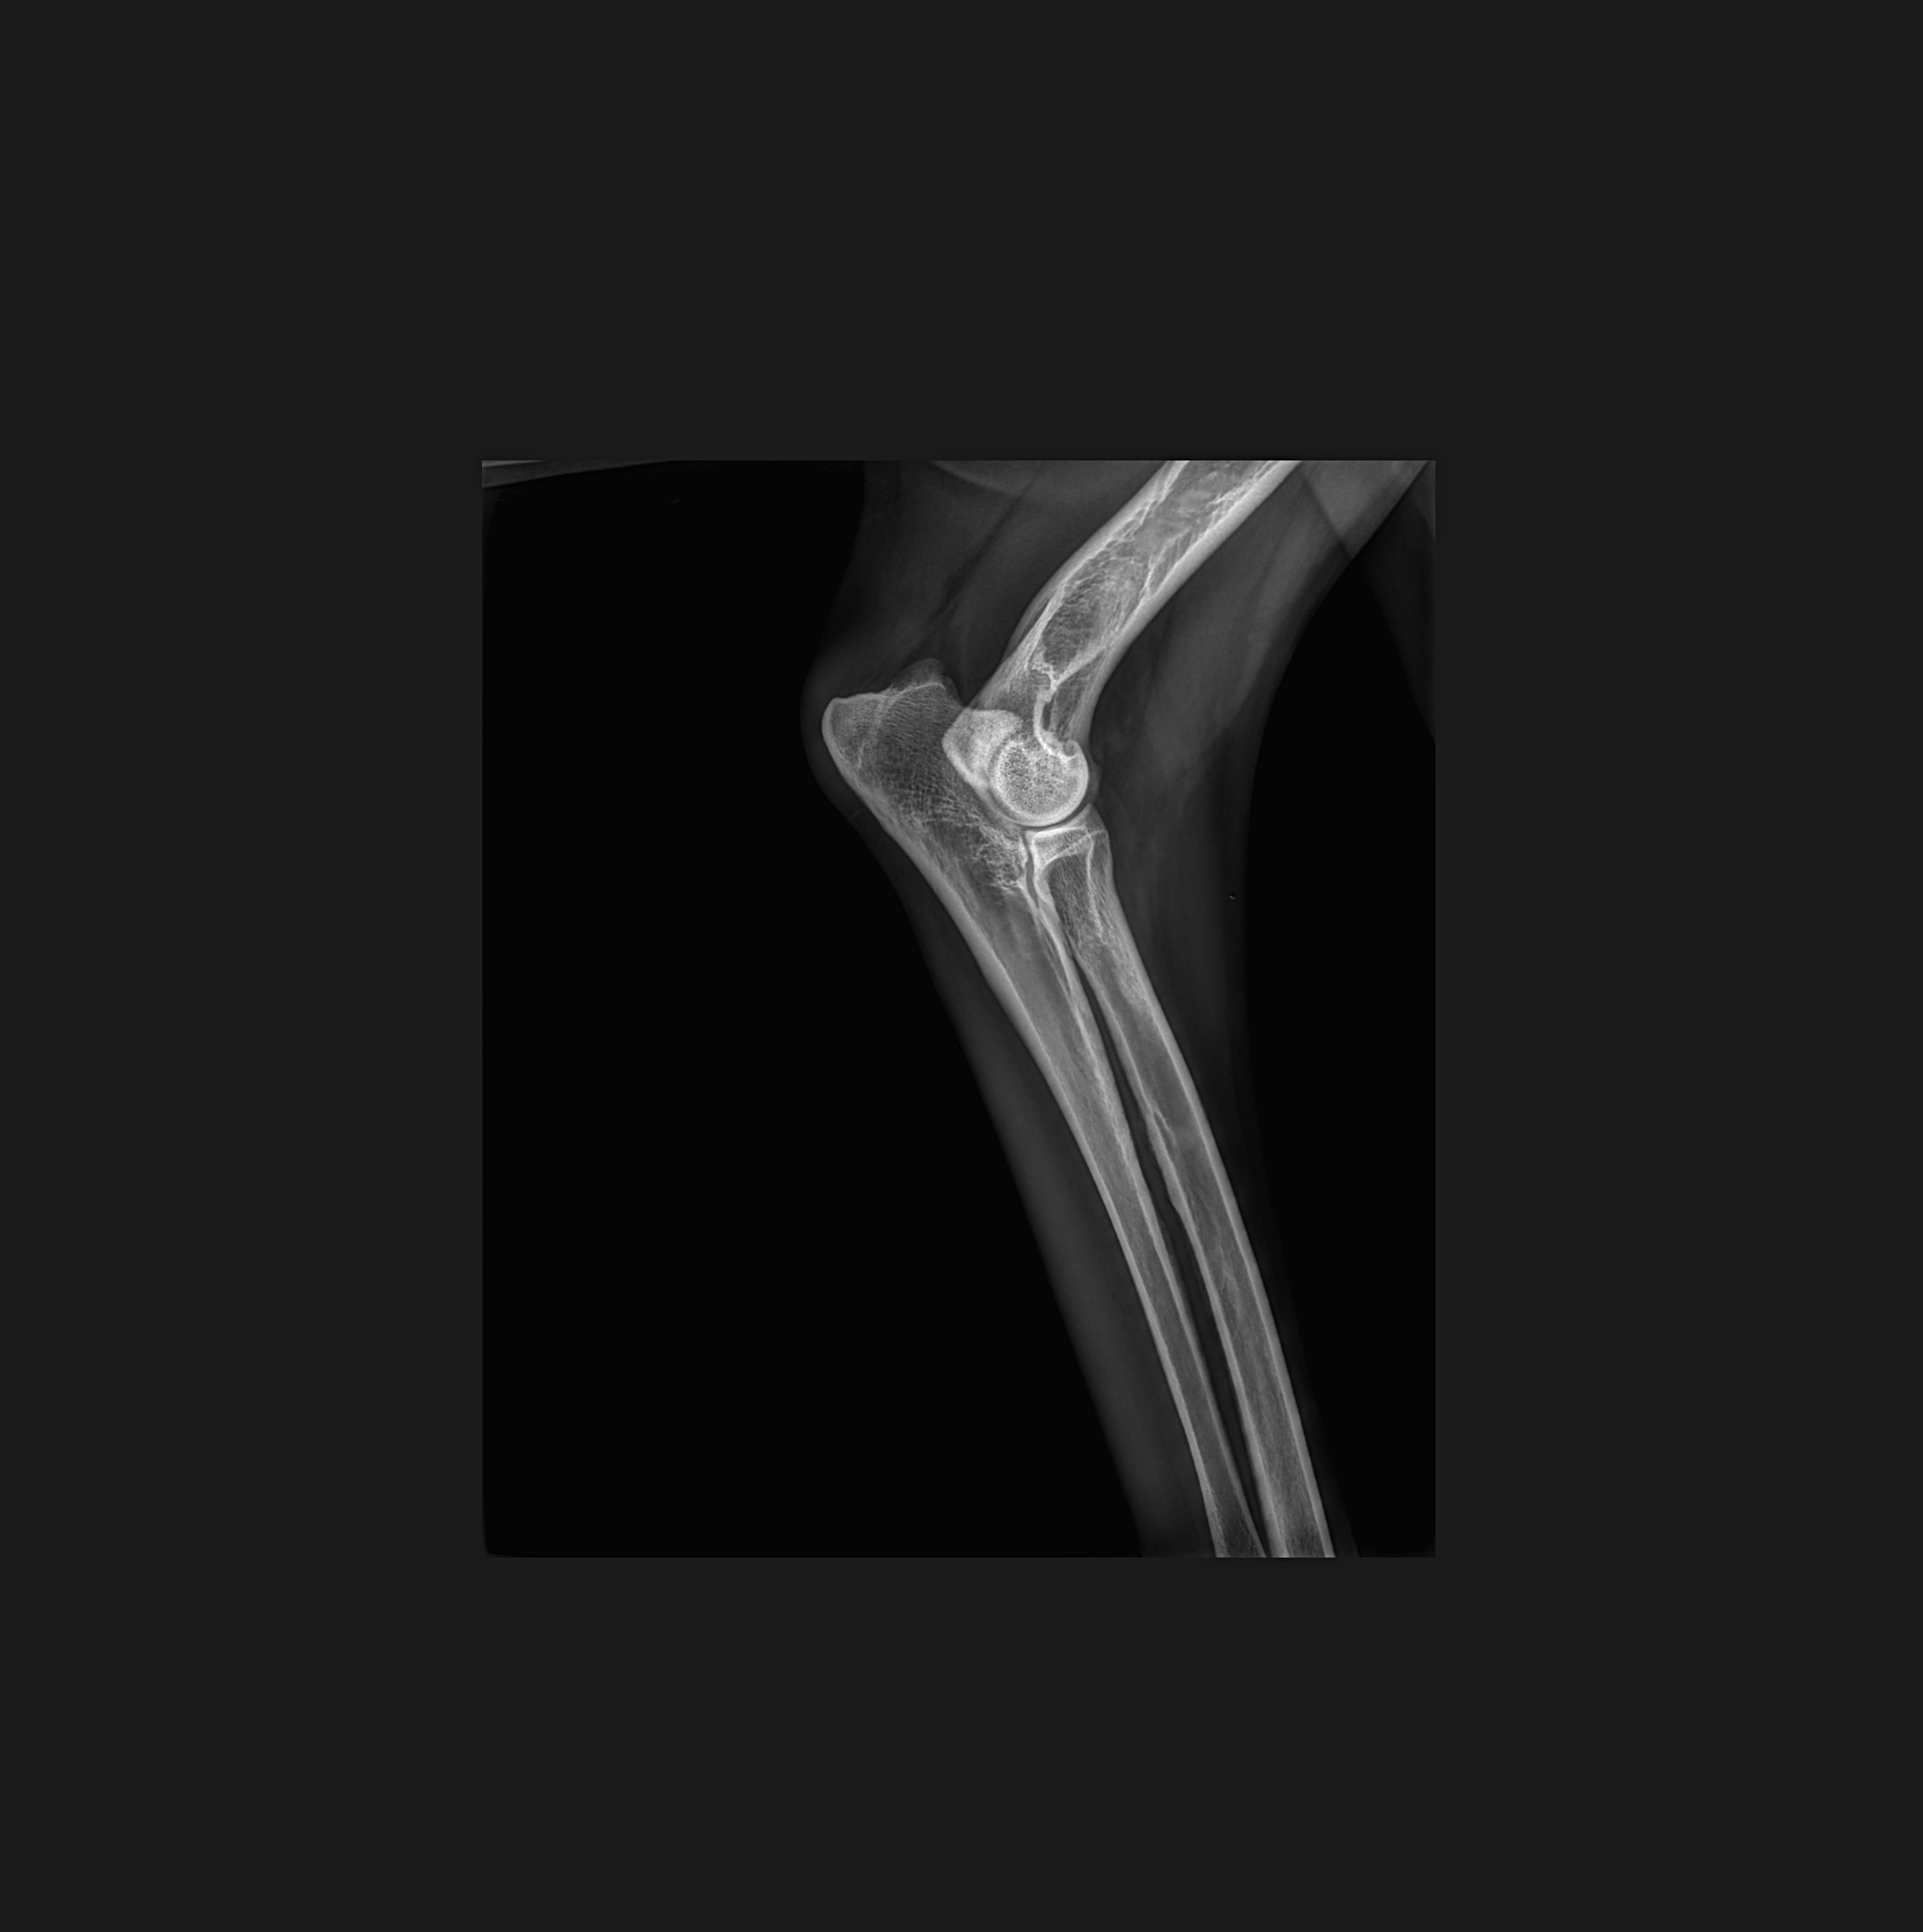

Boiterie à froid antérieur droit

2025-11-07 17:55:28

影像学